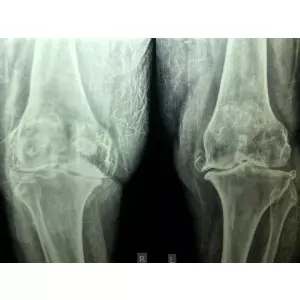

Dr Samir Nanavati